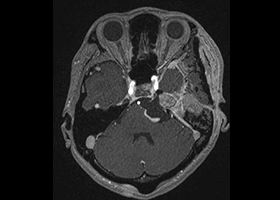

[画像所見]

頭部MRI -

頭部造影三次元CT

左後下小脳動脈が左舌咽神経を圧迫していたために左咽頭部を中心に激しい痛みが生じていました。

術前造影三次元CT -

術後造影三次元CT

左後下小脳動脈(黄色矢印)は術後に本来の位置から移動している。舌咽神経への血管圧迫が解除されたため、術後に患者様は舌咽神経痛が消失した。